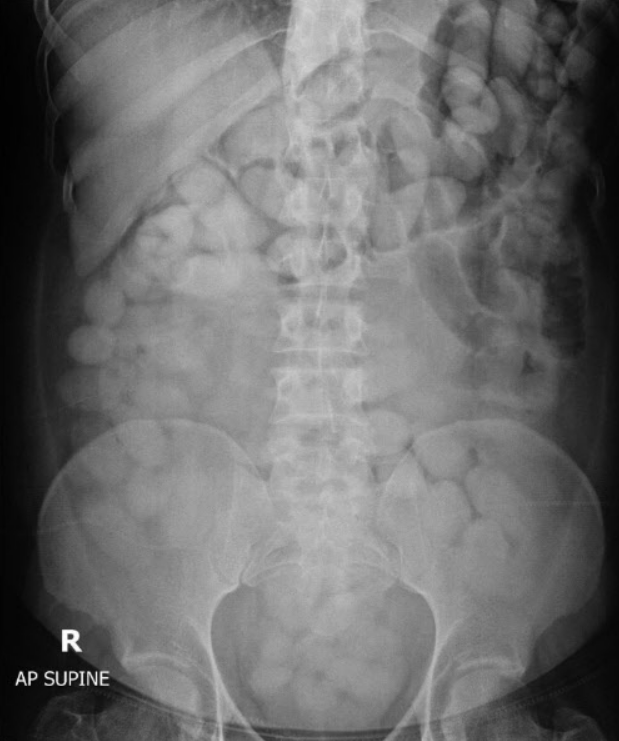

당초 A씨의 사망 원인은 엑스터시 급성 중독으로 알려졌었다. 그런데 부검 결과 A씨의 뱃속에서 마약류인 엑스터시 봉지 79개가 터진 채로 발견됐다. 게다가 그의 장기 안에서는 무려 600여명이 동시에 투약할 수 있는 케타민 분말 118g도 나왔다.

이에 경찰은 A씨가 지난달 태국에서 귀국하며 몸 속에 숨기고 밀반입하려고 한 마약 봉지가 터지면서 사망한 것으로 보고 있다.

보디패커들은 몸 속에서 마약 봉지가 터지면 급사할 수 있어 움직임을 최소화하고 음식물을 섭취하지 않아야 하는 것으로 알려졌다.